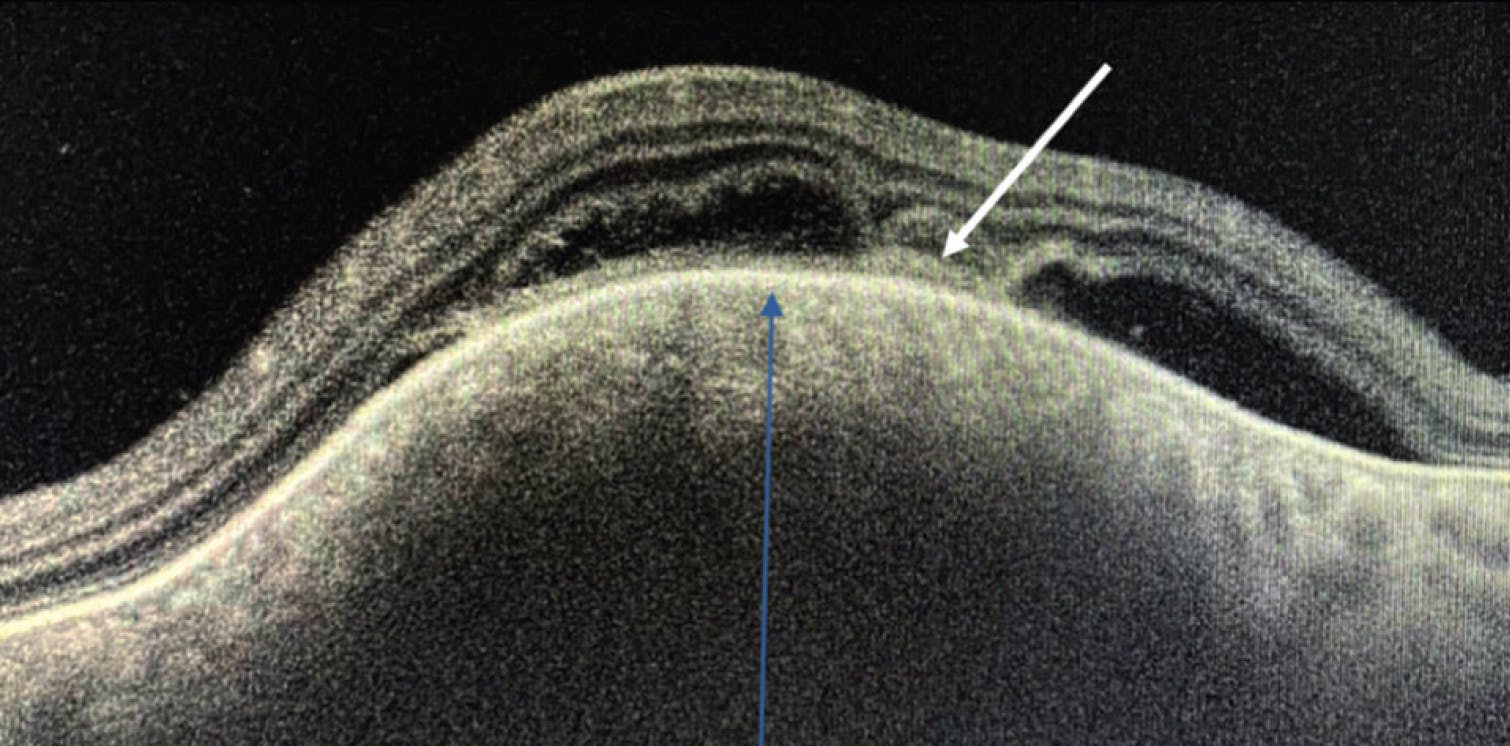

Fundus examination revealed Bouchut tubercles and a choroidal granuloma at the posterior pole (Figure 1). OCT imaging showed a hyporeflective, dome-shaped lesion (Figure 2, blue arrow), with an overlying attachment between the retinal pigment epithelium-choriocapillaris layer and the neurosensory retina, consistent with the contact sign (Figure 2, white arrow), a finding described by Salman et al in 2006.1

The presence of the contact sign is suggestive of a choroidal tuberculoma and contrasts with the OCT features observed in noninflammatory conditions, such as choroidal tumors found in cases of melanoma, metastasis, or circumscribed hemangioma. Management for this case included initiating systemic antitubercular therapy in coordination with infectious disease specialists, along with close ophthalmologic monitoring.